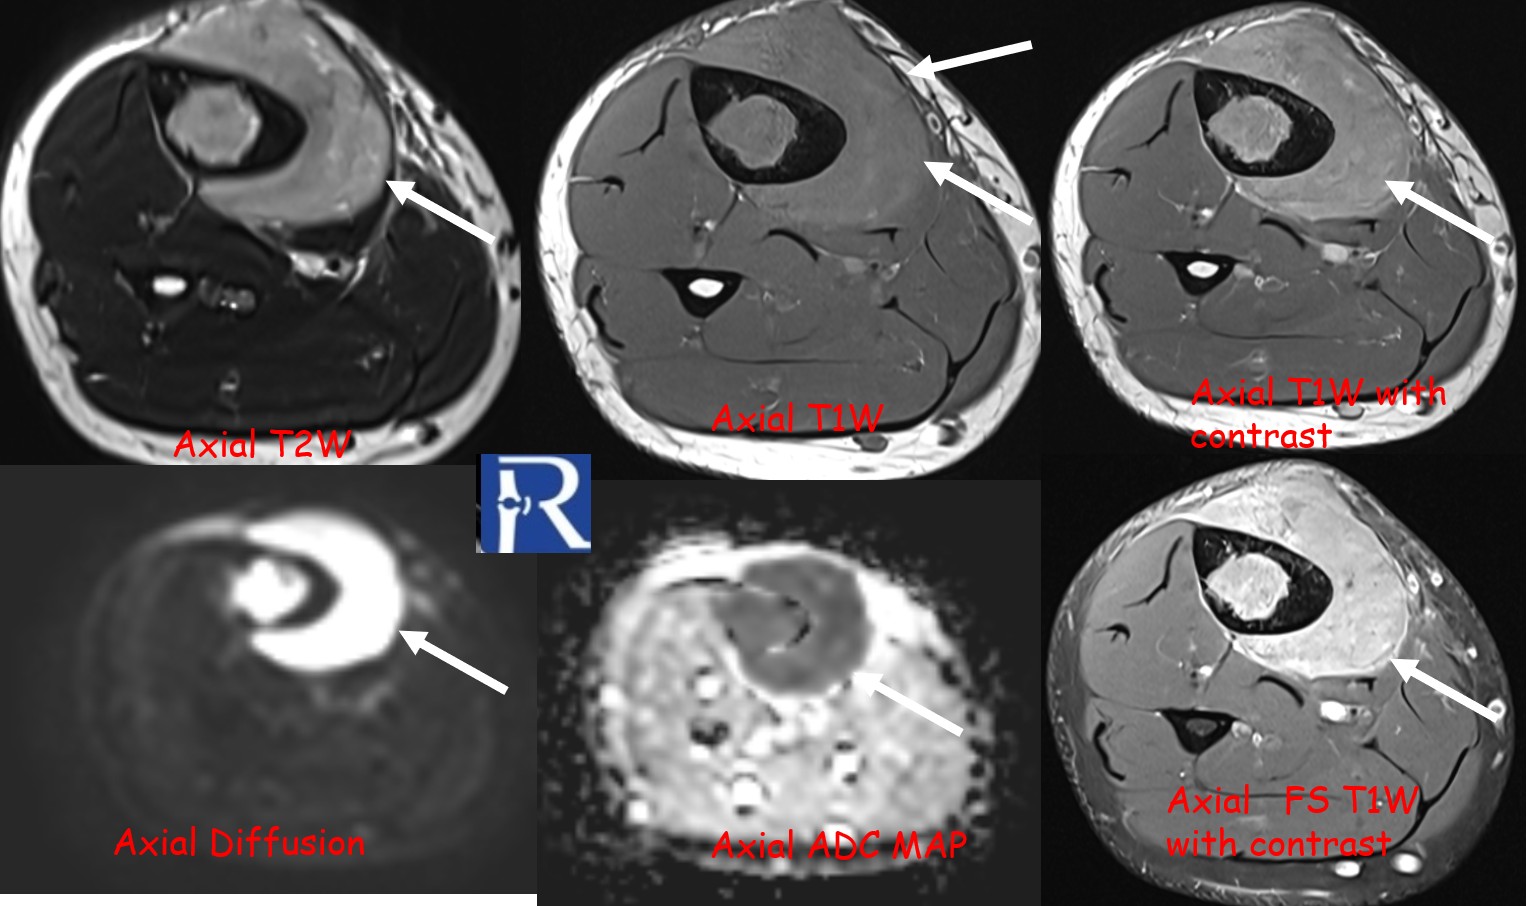

MRI revealed a significant soft-tissue component extending beyond the cortical margin, appearing hypointense on T1-weighted and intermediate on T2-weighted sequences, with heterogeneous contrast enhancement.

Diffusion-weighted imaging (DWI) showed marked diffusion restriction in both osseous and soft-tissue components, reflecting high cellularity.

These imaging findings—particularly the absence of periosteal reaction, intermediate T2 signal, and marked DWI restriction—favored the diagnosis of lymphoma over Ewing sarcoma.

However, certain imaging clues may guide the differential diagnosis. Lymphoma typically demonstrates limited cortical destruction, absence of periosteal reaction, and intermediate T2 signal intensity, whereas Ewing sarcoma tends to produce more prominent periosteal layering and higher T2 hyperintensity. Diffusion-weighted imaging is a powerful adjunct, with strong restriction patterns highly suggestive of lymphoma due to its dense cellular structure.

Diffusion-weighted MRI plays a crucial role in differentiating lymphoma from Ewing sarcoma, reinforcing its value in musculoskeletal tumor imaging.